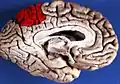

![]() Medial surface of left cerebral hemisphere. (Precuneus visible at top left.) (Anterior to the right.) | |

Precuneus of left cerebral hemisphere (shown in red). -

Medial surface of left cerebral hemisphere. (Precuneus visible at top left.) -

Medial surface of left cerebral hemisphere. (Precuneus colored in red.)